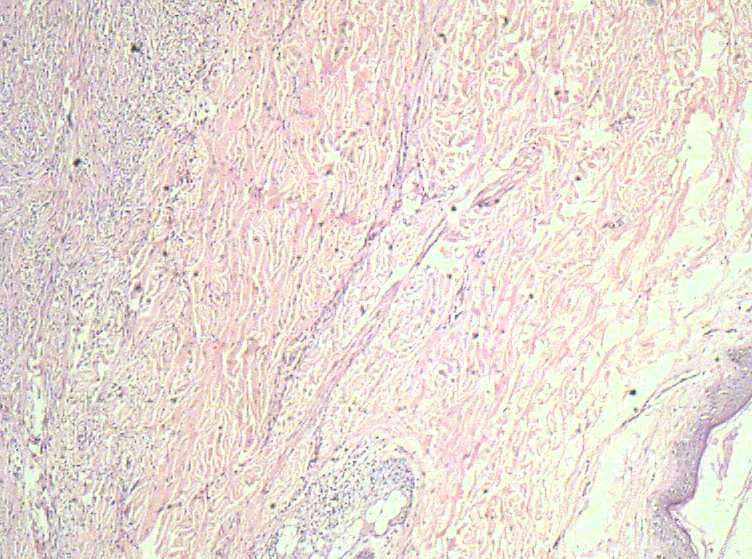

女40岁,发现乳房皮肤表面一年多。

肉眼:不整形组织1.5*1*0.5一侧见皮肤或一侧可见脂肪,切开内一小结节触之稍韧。

倾向于皮肤纤维瘤。

皮肤纤维瘤

良性病变。

炎症后的瘢痕结节或者纤维组织瘤样增生?